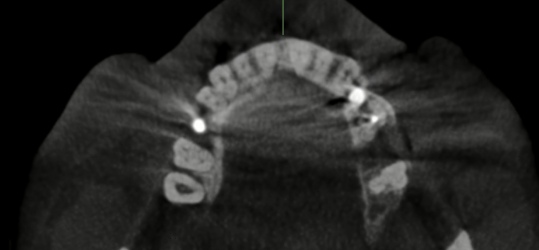

I do have more x rays that I’ll attach here.